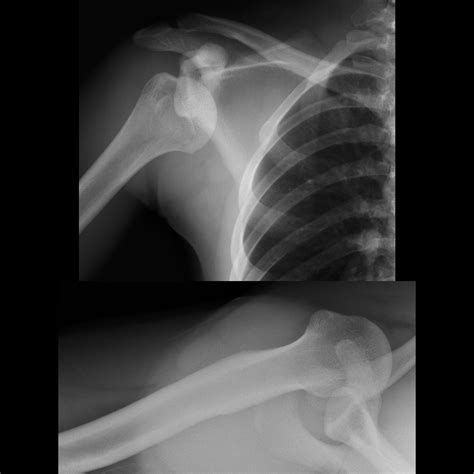

• X-rays: Often the first line of defense for bone fractures or lung issues.

X-ray Minimal Bone fractures, pneumonia, chest congestion